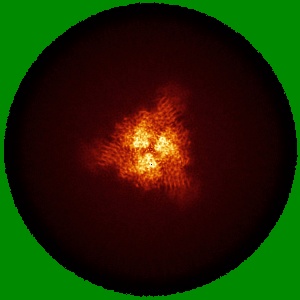

EMD-25986

Down-state locked rS2d SARS-CoV-2 spike ectodomain in the RBD-down conformation, State 2

Single-particle3.06 Å